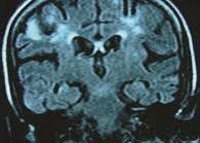

B22.0 Болезнь, вызванная ВИЧ, с проявлениями энцефалопатии